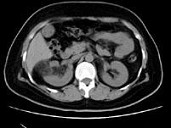

- 多项选择题男,55岁, 右腰部不适1年余,CT扫描如图所示, 下列说法正确的是 ( )

A、右肾中极可见一类圆形肿块影,肿块密度不均

B、其内见低密度脂肪影

C、其边缘清楚,与周围境界清晰

D、考虑为右肾癌

E、考虑为右肾错构瘤